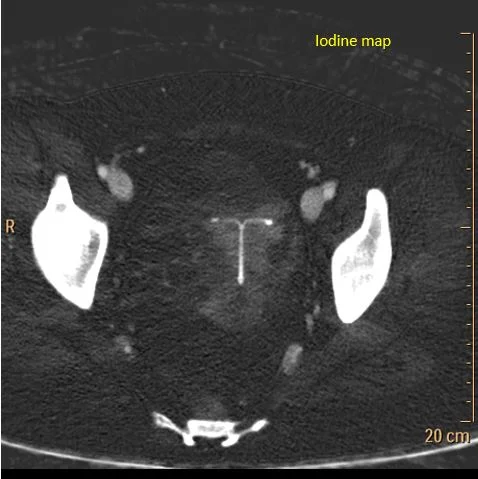

Iodine map: No uptake in the mass. Notice the thin enhancing margin. This is a blood clot inside a cyst.

CT scan obtained in the ED shows a complex right adnexal mass, about 60 HU. Turn on spectral CT, and you see it is made of non-enhancing clot, hyperdense on virtual non-contrast and without iodine uptake, inside the thin, enhancing lining of a cyst. The clot has a spectral curve that is flat, consistent with absent perfusion.